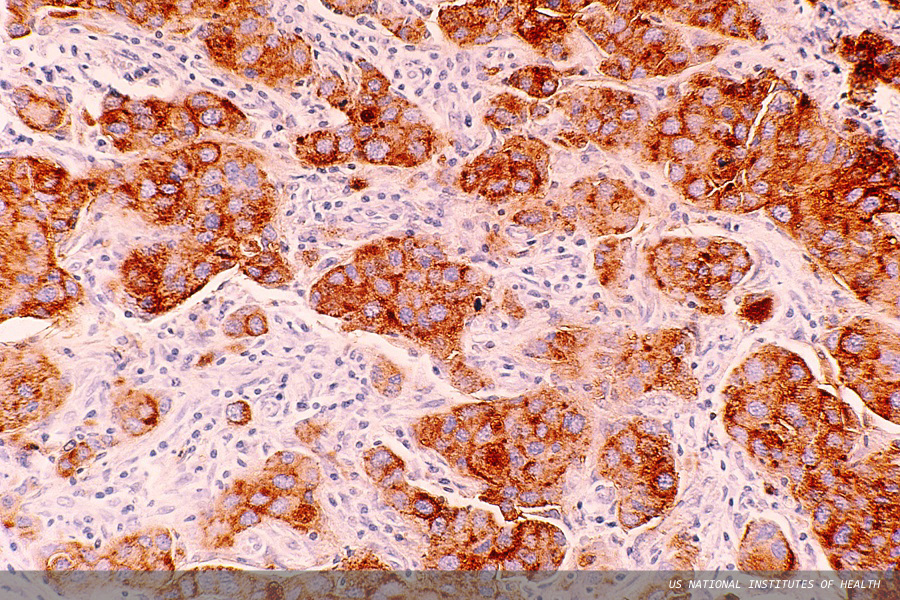

Pictured is an infiltrating ductal carcinoma of breast. The cytoplasm of the tumour cells is stained brown using an immunohistochemistry method to detect carcinoembryonic antigen (CEA).